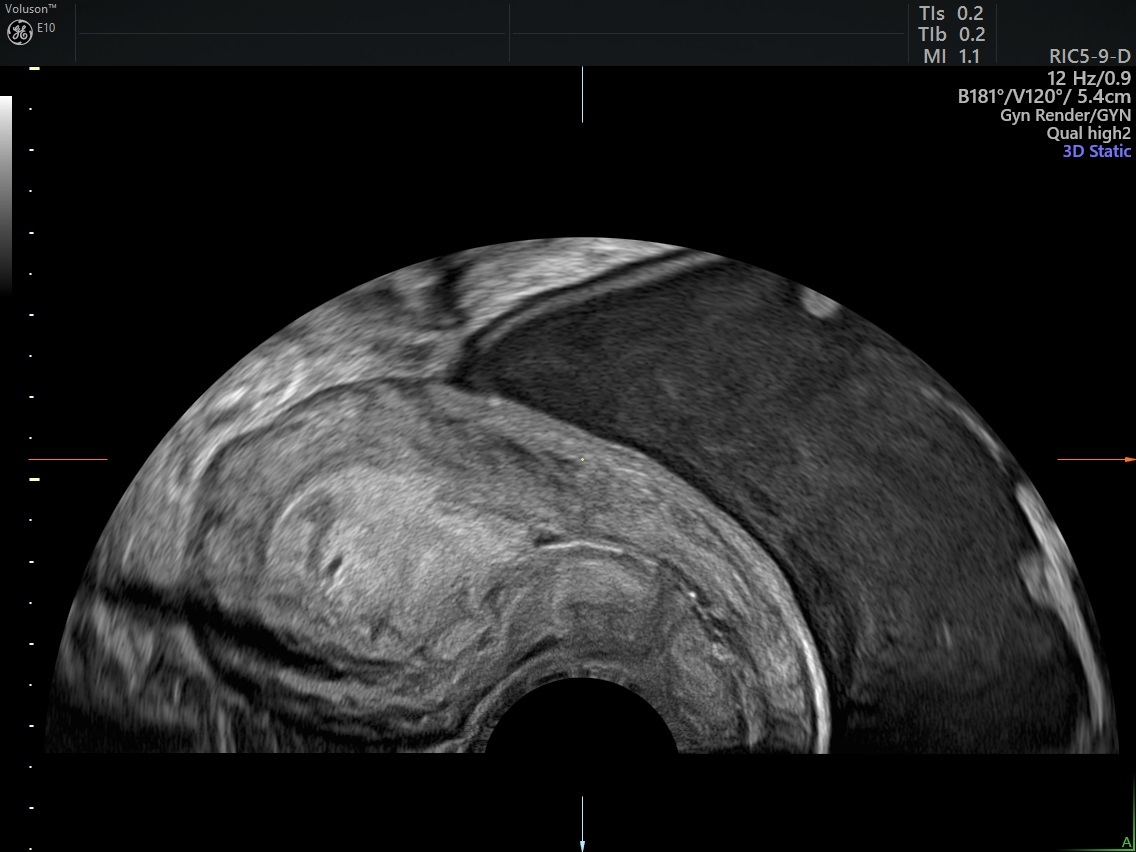

Endometrial/junctional zone thickening Clinical Tree

From clinicalpub.com

Endometrial/junctional zone thickening Clinical Tree Thickened Endometrium After D&C Endometrial hyperplasia is a condition in which the lining of your womb becomes too thick. Endometrial hyperplasia thickens your uterine lining, causing heavy or abnormal bleeding. In some women, this can. Atypical endometrial hyperplasia raises your. A dilation and curettage (d&c) is a procedure to remove tissue from your uterus. The condition is associated with heavy. When there is an. Thickened Endometrium After D&C.